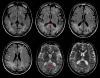

• Gustavo Fernández Pajarín | 31-Aug-2017

Mujer de 66 años diagnosticada de enfermedad de Parkinson avanzada. En noviembre de 2010 se implantó un sistema de ECP subtalámica bilateral, con buen resultado y sin complicaciones. La situación motora de la paciente alcanzó al año...

Caso completo | PDF

Neurología: Trastornos del movimientoEtiología: Tóxica-yatrogeniaDiagnóstico final: Edema y formación quística circundantes a electrodo de estimulación cerebralNivel de certeza: